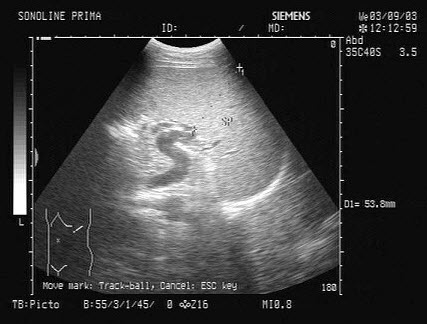

某患者脾脏声像图表现如图,诊断为()